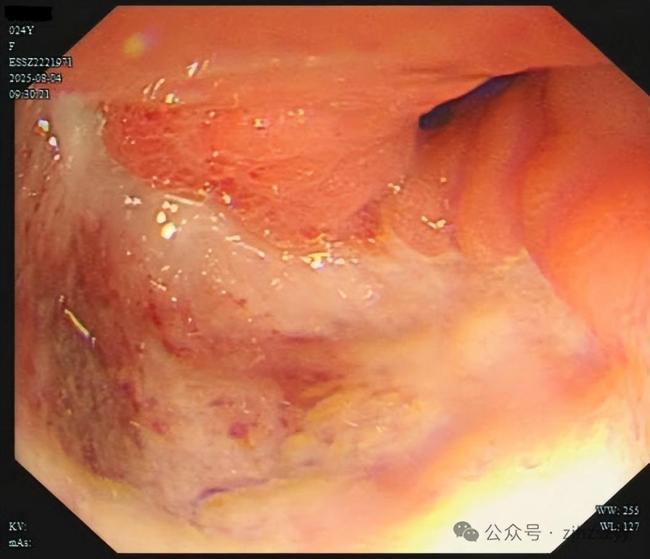

直到她开始频繁出现黑便,并在片场拍戏时几次呕血,才被同事紧急送往医院急诊。医生立即为她安排了急诊胃镜检查,发现她整个胃窦被巨大的溃疡占据,黏膜组织变得僵硬、缺乏弹性。随后的活检结果显示,她患上了胃印戒细胞癌。

小雯所患的印戒细胞癌被称为“胃癌之王”,是胃癌中一种恶性程度极高的类型,占胃癌恶性肿瘤的10%左右。这种癌症的特点是隐匿性强,在胃镜下表现不明显,识别非常困难。早期患者很多没有明显的症状,或者症状和普通消化道疾病相似,极易被忽视。多数发现时已是晚期,且具有很强的侵袭力,易转移,病情进展快。晚期患者的生存期一般只有6-12个月,5年生存率几乎为零。